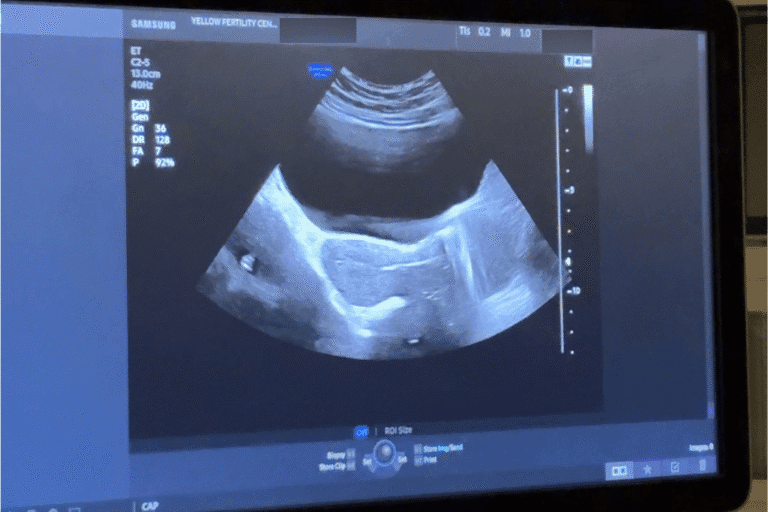

This is why it is important to assess patients’ uterine health through ultrasound, hysteroscopy, or other diagnostic tools before embryo transfer. At Yellow IVF, our best IVF specialist in Gurgaon follows a multidisciplinary approach to offer comprehensive care to patients under one roof.